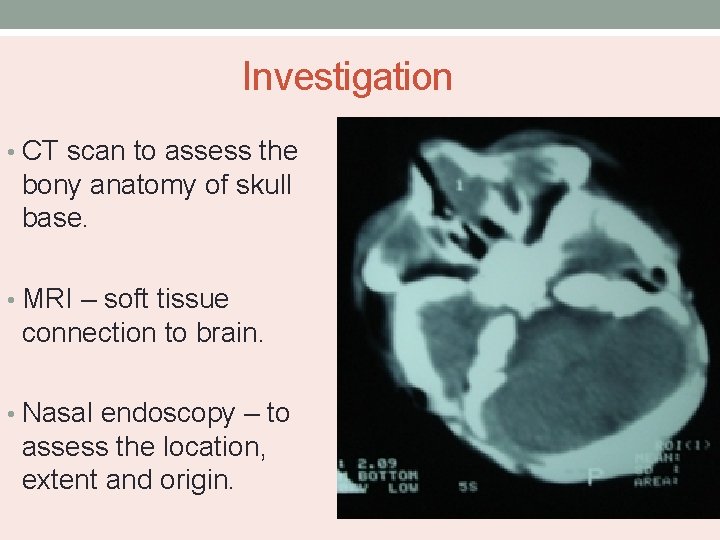

Investigation • CT scan to assess the bony anatomy of skull base. • MRI – soft tissue connection to brain. • Nasal endoscopy – to assess the location, extent and origin.